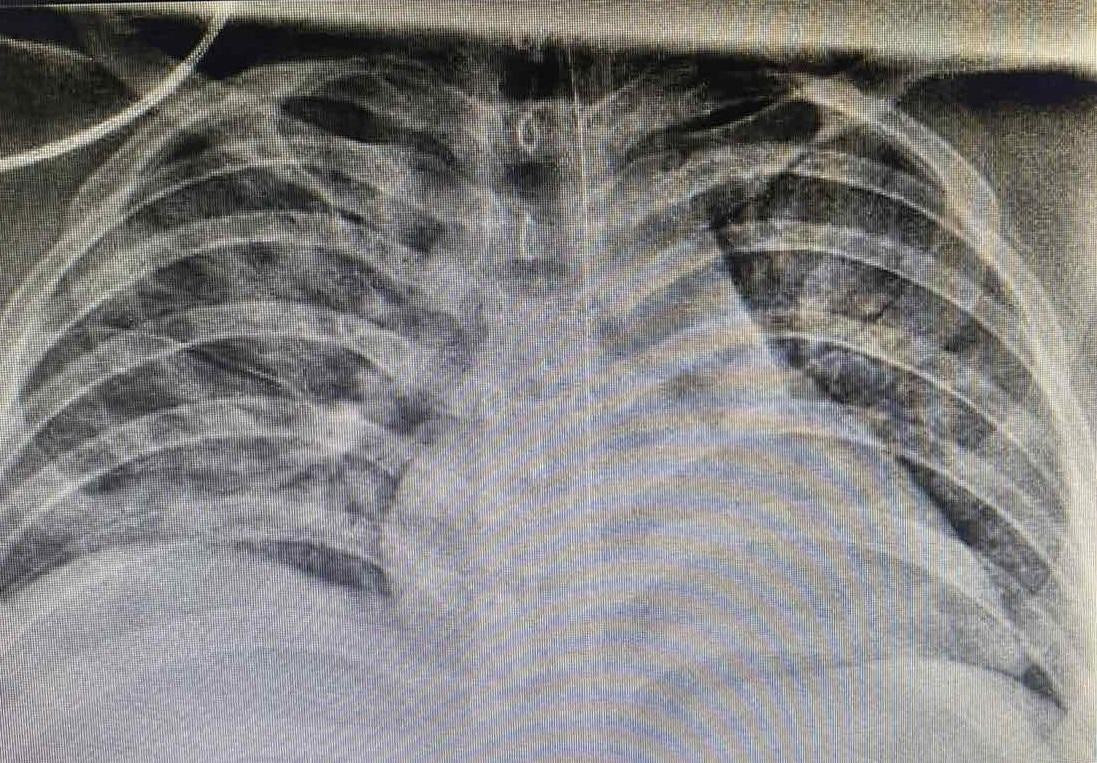

| Thời điểm mới nhập viện, phổi bệnh nhân bị tổn thương rất nặng trên nền cơ địa béo phì mắc COVID-19. |

Tuy nhiên, tình trạng không cải thiện, hình ảnh X-quang phổi cho thấy, bệnh nhân bị tổn thương phổi nặng lan tỏa hai bên. Các bác sĩ đã tiến hành hội chẩn và nhận định trẻ có biểu hiện hội chứng suy hô hấp cấp tiến triển (ARDS) nên ê kíp điều trị quyết định đặt nội khí quản cho thở máy.